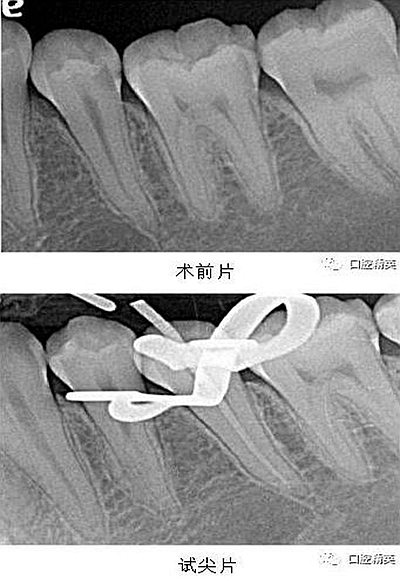

X-ray 可見:35 遠(yuǎn)中齲壞累及髓腔,牙周膜增寬。

處置:經(jīng)患者及家屬知情同意后,35 局麻,放置橡皮障,去腐,開髓,可見黑色感染物流出,定位根管口,建立直線通路,10# K 銼疏通根管,確定工作長度(19mm),機用鎳鈦器械(M3),次氯酸鈉全程浸泡沖洗,預(yù)備根管至 35 號,0.04 錐度,2ml EDTA 沖洗液緩慢勻速沖洗,超聲蕩洗。試主尖 X-ray 可見恰充,吸潮紙尖拭干根管,導(dǎo)AH-Plus 糊劑,連續(xù)波熱牙膠垂直加壓充填,術(shù)后 X-ray可見根管恰充,SDR 封閉根管口,復(fù)合樹脂充填窩洞,恢復(fù)牙齒形態(tài),調(diào)牙合,拋光。醫(yī)囑